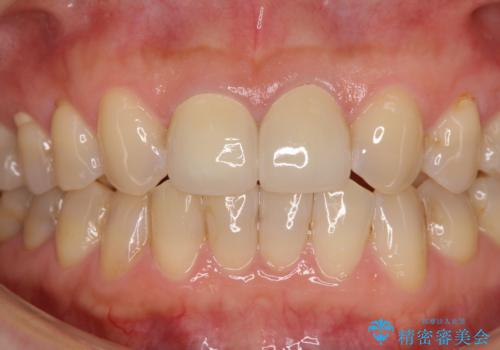

2本ともに虫歯治療による充填材の変色などによりつぎはぎのような前歯となっていたため、オールセラミッククラウンにて補綴治療を行うこととしました。

今後ホワイトニングをする予定とのことで、少し明るめのトーンに仕上げました。